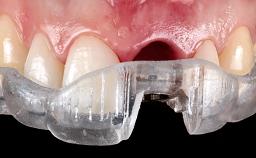

This case from Amélie Mainjot and France Lambert shows how the choice of a screw-retained restoration—which allows adjustment of the profile design over time—was key to managing complications successfully. The authors’ strategic approach avoided a crown remake while also compensating for a soft tissue mismatch. A healthy 20-year-old woman, a non-smoker, presented at the emergency department of the University Hospital of Liège in February 2011 with multiple vertical fractures of tooth 21, incisal fractures of tooth 31, and an enamel and dentin fracture of tooth 32. No tooth luxation was observed. Radiographs confirmed multiple root fractures on tooth 21, including a vertical infrabony fracture, indicating that the tooth was not restorable. A pulpectomy of tooth 21 and an indirect pulp cap on tooth 32 using resin-modified glass-ionomer cement (RMGIC) (Vitrebond; 3M, St. Paul, MN, USA) were performed. RMGC (Fuji IILC; GC, Tokyo, Japan) provisional restorations were placed on the injured teeth. The patient was sent for 3D imaging (multislice CT) the next day to determine the replacement strategy for tooth 21. Because of the vertical fractures, it was important to extract tooth 21 within a few days after the trauma to limit the risk of bacterial infection and consequent tissue loss.